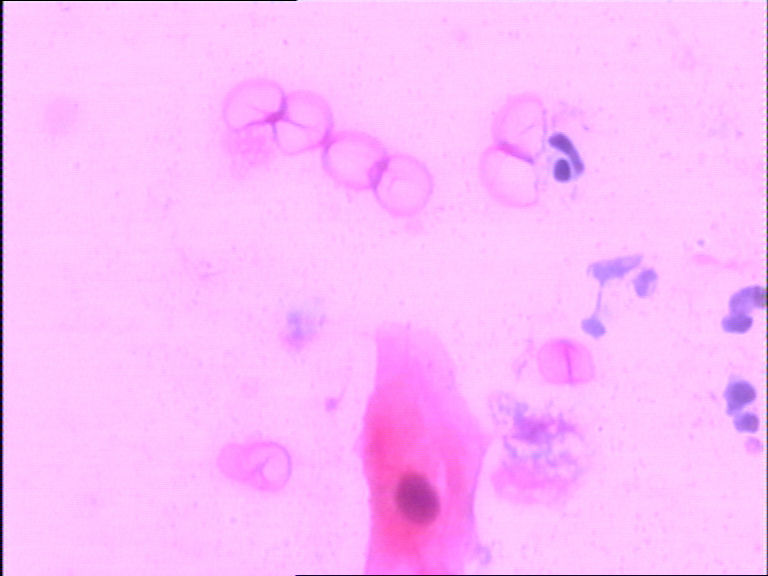

患者女38岁,宫颈TCT,巴氏染色。镜下有许多小细胞,胞膜较厚,胞浆较空,核呈长杆状。考虑是不是生物制品。求教各位老师。

图1

图2

图3

图4

图5

图6